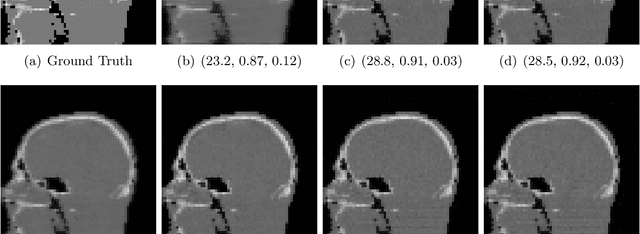

Abstract:Image quality assessment (IQA) is standard practice in the development stage of novel machine learning algorithms that operate on images. The most commonly used IQA measures have been developed and tested for natural images, but not in the medical setting. Reported inconsistencies arising in medical images are not surprising, as they have different properties than natural images. In this study, we test the applicability of common IQA measures for medical image data by comparing their assessment to manually rated chest X-ray (5 experts) and photoacoustic image data (1 expert). Moreover, we include supplementary studies on grayscale natural images and accelerated brain MRI data. The results of all experiments show a similar outcome in line with previous findings for medical imaging: PSNR and SSIM in the default setting are in the lower range of the result list and HaarPSI outperforms the other tested measures in the overall performance. Also among the top performers in our medical experiments are the full reference measures DISTS, FSIM, LPIPS and MS-SSIM. Generally, the results on natural images yield considerably higher correlations, suggesting that the additional employment of tailored IQA measures for medical imaging algorithms is needed.

Abstract:Image quality assessment (IQA) is not just indispensable in clinical practice to ensure high standards, but also in the development stage of novel algorithms that operate on medical images with reference data. This paper provides a structured and comprehensive collection of examples where the two most common full reference (FR) image quality measures prove to be unsuitable for the assessment of novel algorithms using different kinds of medical images, including real-world MRI, CT, OCT, X-Ray, digital pathology and photoacoustic imaging data. In particular, the FR-IQA measures PSNR and SSIM are known and tested for working successfully in many natural imaging tasks, but discrepancies in medical scenarios have been noted in the literature. Inconsistencies arising in medical images are not surprising, as they have very different properties than natural images which have not been targeted nor tested in the development of the mentioned measures, and therefore might imply wrong judgement of novel methods for medical images. Therefore, improvement is urgently needed in particular in this era of AI to increase explainability, reproducibility and generalizability in machine learning for medical imaging and beyond. On top of the pitfalls we will provide ideas for future research as well as suggesting guidelines for the usage of FR-IQA measures applied to medical images.